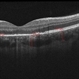

- Unilateral Acute Idiopathic Maculopathy

- chorioretinal inflammations, unilateral acute idiopathic maculopathy, Coxsackie

- Kidron Robertson, Georgia Eye Institute of the Southeast, Savannah, GA

Optical coherence tomography system

Heidelberg Spectralis - Description

- Infrared photo shows subtle RPE changes on inferior edge of fovea. OCT does not show any significant RPE or IS/OS disruption.